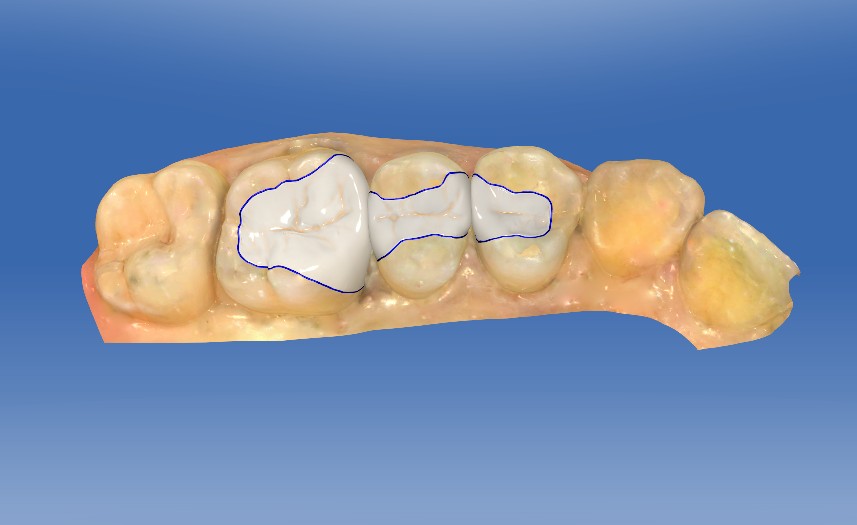

0.1%的聚维酮碘溶液局部消毒,涂表麻膏,4%盐酸阿替卡因肾上腺素注射液0.8ml局部浸润麻醉,等待麻药生效后。去净腐质,基牙预备基牙预备,排龈,精修,CEREC扫描,比色,CEREC制作嵌体,试戴后边缘密合,符合各种对修复体的质量和设计要求,患者满意,同意粘固。消毒基牙和修复体,酸蚀冲洗,隔湿,吹干,粘接做永久固定,调合抛光,交代注意事项,常规医嘱,按时复诊,客户表示一次就诊方便快捷,很满意。